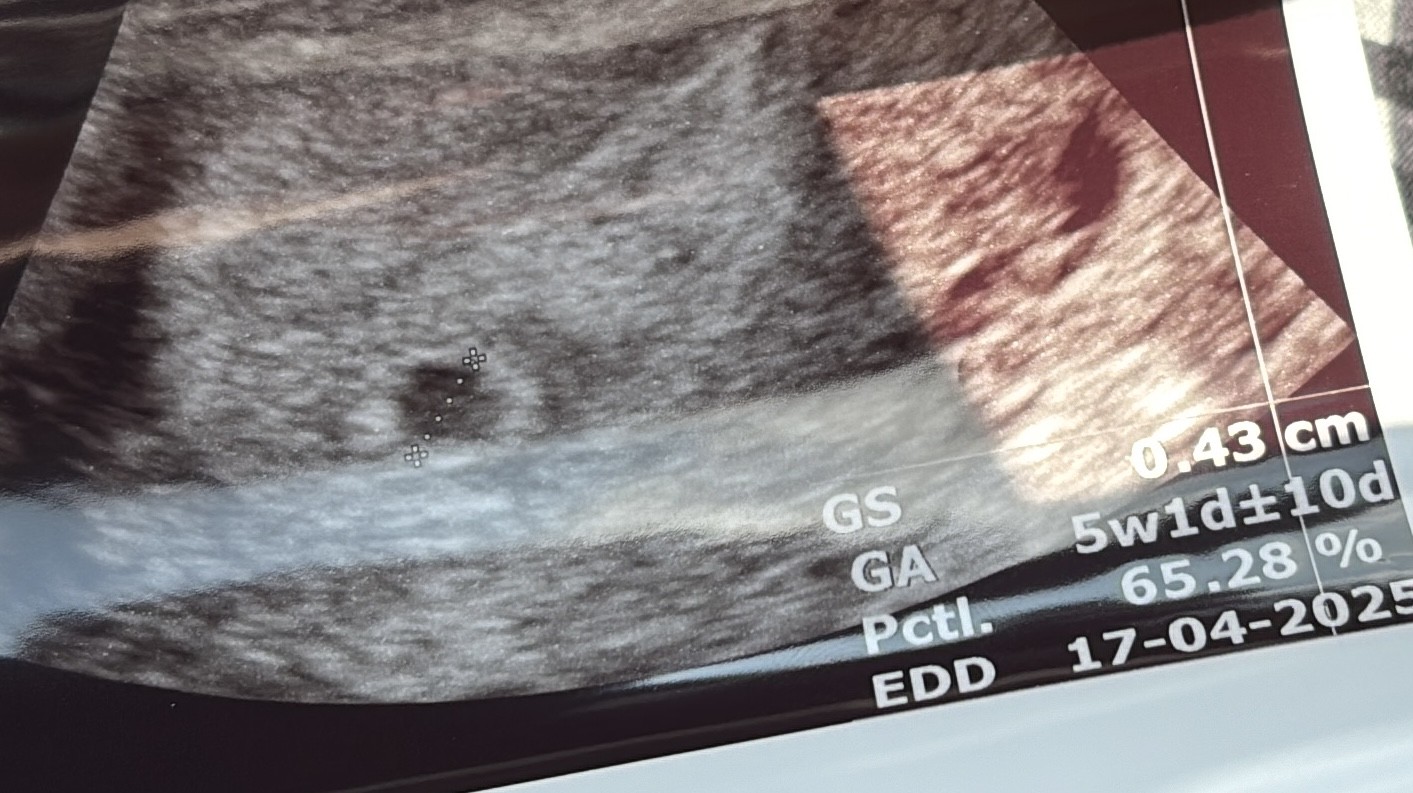

Czy to ciąża bliźniacza ?

Hej , byłam tydzień temu u ginekologa podczas badania poza oznajmieniem że jestem w ciąży powiedział mi że widzi podwójną owulację i jest zbyt wcześnie by widzieć coś więcej (5tydzien +2 dzień) . Powiedzial ze za miesiąc się dowiem czegoś więcej na wizycie . Czy jestem w ciąży bliźniaczej ? Ta myśl nie daje mi spokoju

• 9715727D-84DD-421E-8F96-AF1E0C7EEEF5.jpeg

9715727D-84DD-421E-8F96-AF1E0C7EEEF5.jpeg

245,9 KB · Wyświetleń: 435